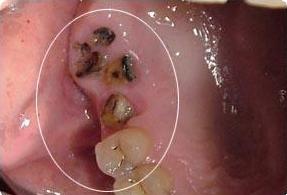

首先科普一下什么是残根。我们把一颗牙齿比作一颗"大树",牙科疾病好似"虫子",一直在不断攻击牙齿这颗"大树",最后只剩下树根。我们通常把这种残缺程度的牙齿称为残根。

针对残根的去留问题,主要是基于两方面的考虑。一方面是患牙是否有炎症,炎症是否可以通过控制和治疗来维护口腔健康;另一方面是患牙经过治疗后能否恢复功能,像残根过短不能利用也是要拔除的。

不管最终决定要不要残根,残根一定不要放任不管。残根使牙齿的髓腔、根管暴露于口腔充满细菌的环境中,进一步还可以引起全身的其它疾病。

牙根残缺会导致食物嵌塞,清洁不到位造成细菌感染,诱发牙龈炎、龋齿等一系列牙科疾病。最严重的情况牙齿出现松动,一旦咀嚼硬物容易崩牙或脱落。

残根会不定期刺激摩擦损伤口腔内的粘膜,会让娇嫩的口腔粘膜吃不消,容易形成创伤性溃疡。同时也大大提高了患癌风险,易引发舌癌、口腔癌等后果。